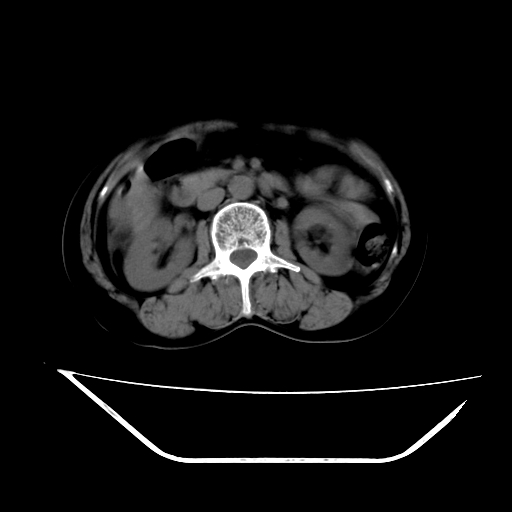

ct增强

考虑肝腺瘤出血可能,肝血管瘤增强表现不是很典型,放在第二。

6月份ct片显示肝内巨大混杂密度团块,伴包膜下积液(内含液液平面),增强多无明显强化。只能考虑肝占位病变,并肝内、血膜下血肿。肝ca并出血多见,而肝血管瘤并破裂出血少见。

6月份ct片显示肝内巨大混杂密度团块,伴包膜下积液(内含液液平面),增强多无明显强化。只能考虑肝占位病变,并肝内、包膜下血肿。肝ca并出血多见,而肝血管瘤并破裂出血少见。